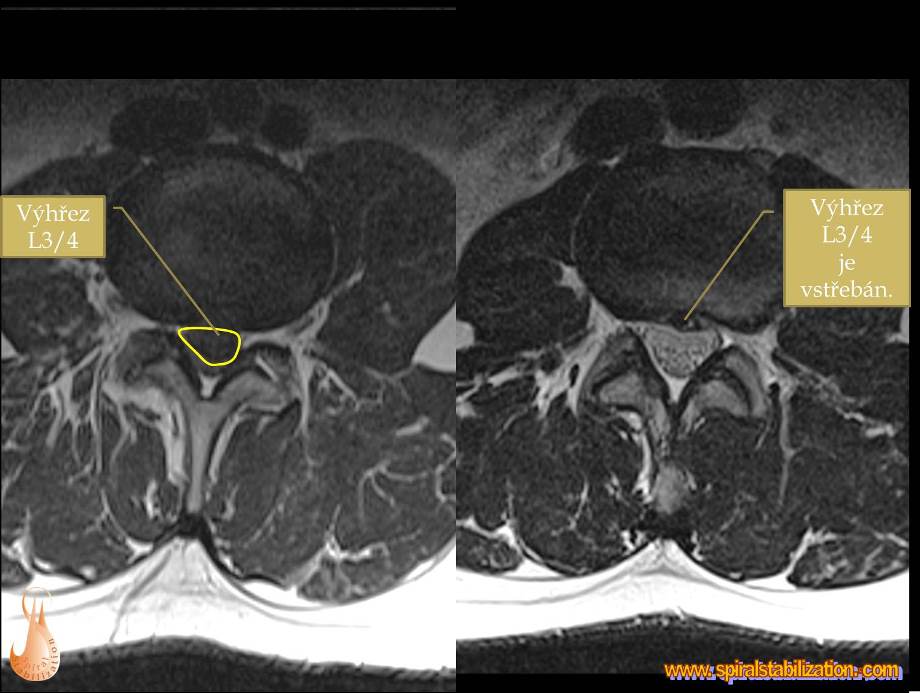

Výsledky hernia L3/L4